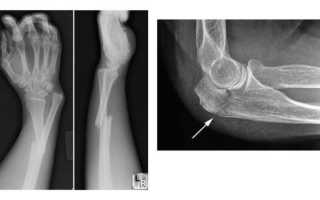

Диагностика перелома предплечья

Специалист сможет установить диагноз после клинического обследования, которое включает в себя пальпацию поврежденной области, внешний осмотр и общение с пациентом. Тем не менее, для окончательной и точной диагностики требуется проведение рентгенологического исследования.

Кроме того, важно определить наличие переломных вывихов, так как игнорирование повреждений капсулы локтевого сустава может привести к серьезным последствиям.